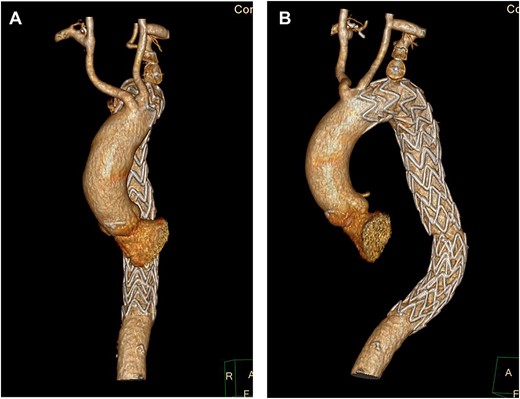

Despite optimal anti-impulse therapy, the patient had refractory chest/upper back pain. The patient underwent a left C-S bypass and right subclavian to common carotid artery transposition (with oversewing of proximal subclavian stump). This was followed by deployment of covered thoracic endovascular graft (Navion, Medtronic) from left common carotid artery (CCA) to 5 cm proximal to celiac artery proximally. The left subclavian artery was occluded using endovascular plugs. His postoperative 2-week CT showed good stent apposition and no endoleak (Fig. 4A, B). He was discharged Day 14 and returned to regular work at 1-month time interval.

(A) 3D-CT reconstruction showing post op repair and Right subclavian to carotid transposition. (B) 3D-CT reconstruction showing post op repair and left C-S bypass.